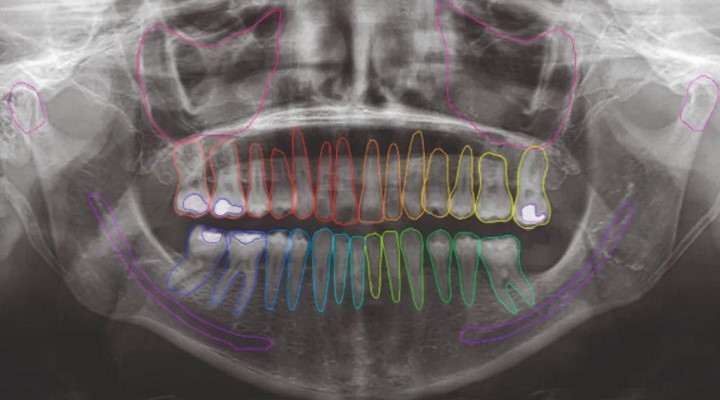

Neowise gives you a complete view of each patient’s diagnostic journey, from X-rays and CBCT scans to 3D renders and treatment simulations, all in one place. Everything is securely stored and instantly accessible through a single, intuitive dashboard.

Using patented AI tools, it automatically identifies anatomical structures, traces nerves, segments images, and highlights potential issues in both panoramic and intraoral views.